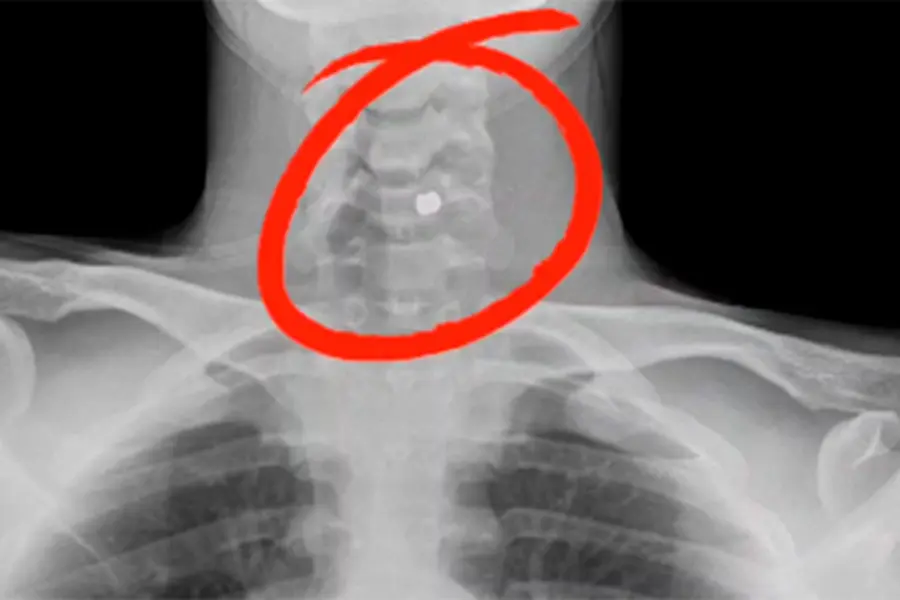

Felipe Rosales y la bala alojada.

Felipe fue baleado mientras circulaba como acompañante en una moto por la calle Ramírez, entre España y Colón, lo que le causó una herida grave en el cuello. El proyectil quedó alojado en su cuerpo y, aunque logró llegar al hospital con vida, su situación médica sigue siendo delicada.

El padre de Felipe, José Luis Rosales, se mostró agradecido por los mensajes de apoyo recibidos, pero también expresó su preocupación por el futuro de su hijo. En diálogo con Canal 5 Univisión, José Luis explicó que, a pesar de que Felipe está fuera de peligro, las lesiones requieren un tratamiento de alta complejidad. “Si Dios quiere, hoy lo traemos a Tala, pero el proyectil va a quedar alojado en su cuello. Si el cuerpo no lo rechaza, podría quedarse ahí por el resto de su vida”, detalló el padre.

La bala alojada en el cuerpo del joven.